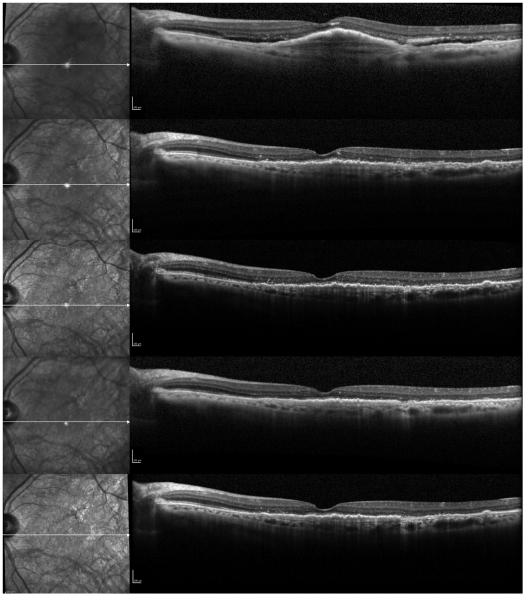

Figure 1.

A case of a 79-year-old female with recurrent fluid who has received 27 previous bevacizumab injections, and was subsequently switched to every 8 weeks intravitreal aflibercept injections. Progression scans going through the fovea at baseline and subsequent follow-ups at 1 month, 2 months, 4 months, and 6 months after switching to aflibercept show a decrease in the height of the subfoveal fibrovascular pigment epithelial detachment (PED), resolution of the subretinal fluid (SRF), and focal disruption of the photoreceptor layer.